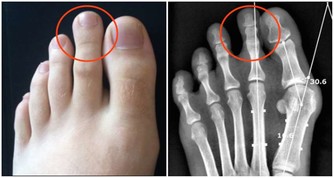

2、發紺

這是一種身體特定區域變成紫色的醫學症狀。

皮膚顏色青紫說明身體某個部位得不到充足的氧氣,青紫的原因可以是任何疾病或者紊亂。

可以很容易從身體皮膚表面看到發紺。

急性發紺的主要根源是心臟衰竭,窒息,休克,左心衰竭等。

此外,有一些原因可導致慢性發紺。

如肺部疾病,慢性阻塞性肺病,先天性心臟病和心臟衰竭等。